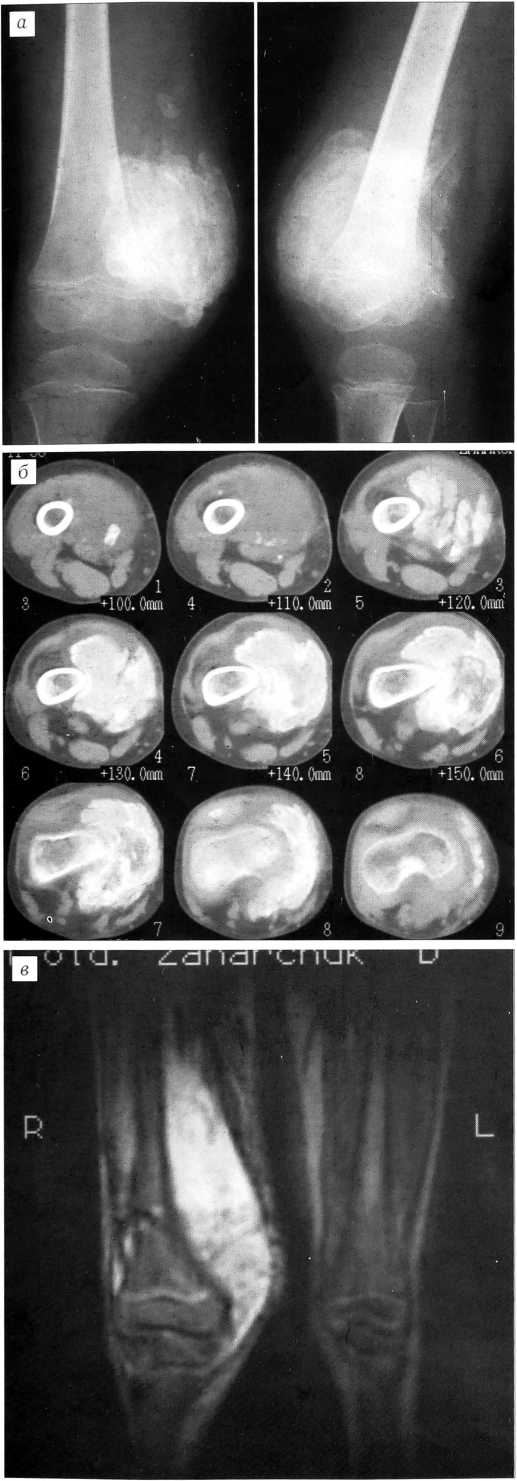

На рентгенограммах правого бедра определяется дополнительное пароссальное лентовидное образование костной плотности с неровным нечетким контуром, располагающееся по ходу мышечных волокон. Поверхность бедренной кости четкая, ровная, периостальных наслоений нет (рис. 1, а) Компьютерная томография: пароссальное образование локализуется в толще m. vastus lateralis, имеет костную плотность и на протяжении 2 см связано с бедренной костью (рис. 1, б, в). Магнитно-резонансная томография в режиме Т2 взвешенности: пароссальное образование имеет гиперинтенсивный, гетерогенный сигнал (рис. 1, г). Выявленные изменения расценены как гетеротопический оссификат.

Рис. 1. Больной У. Гетеротопический оссификат правого бедра. а — рентгенограмма правого бедра: пароссальный оссификат лентовидной формы с четкими контурами по ходу m. vastus lateralis; б — компьютерная томограмма: пароссальный оссификат связан с бедренной костью и располагается в толще мышцы по ходу ее волокон; в — компьютерная томограмма: пароссальный оссификат в режиме 3D реконструкции; г — магнитно-резонансная томограмма: гиперинтенсивный гетерогенный сигнал в режиме Т2 взвешенности.

Через 4 мес после травмы произведена операция. Оссификат полностью располагался в толще наружной порции четырехглавой мышцы, проксимальный отдел его был спаян костным мостиком 2x2 см с наружной поверхностью бедренной кости. Оссификат отсечен долотом. Костная рана покрыта парафином. Активное дренирование ложа оссификата в течение 1 сут. Четырехкратное инфильтрирование краев раны раствором гидрокортизона (50 мг в 10 мл новокаина) с интервалом 1-3 сут. Иммобилизация. Восстановительное лечение через 18 дней. Лечение ксидифоном 3 мес.